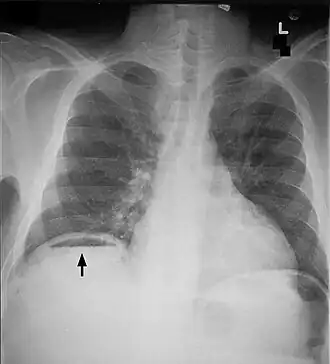

| Raio X de tórax frontal. A bolha de ar abaixo do hemidiafragma direito (no lado esquerdo da imagem) é um pneumoperitônio | |

O diagnóstico é habitualmente realizado pela radiografia (tórax e abdome), sendo o achado mais freqüente a presença de ar intraperitoneal no quadrante superior direito do abdome. O pneumoperitônio torna-se radiologicamente evidente quando a quantidade de ar no abdome oscila entre 30–90 cm.

Pode-se observar na radiografia o sinal de Rigler, que é a visualização das paredes dos intestinos. No exame físico pode-se observar o sinal de Jobert, que é o aparecimento de hipertimpanismo na região hepática.